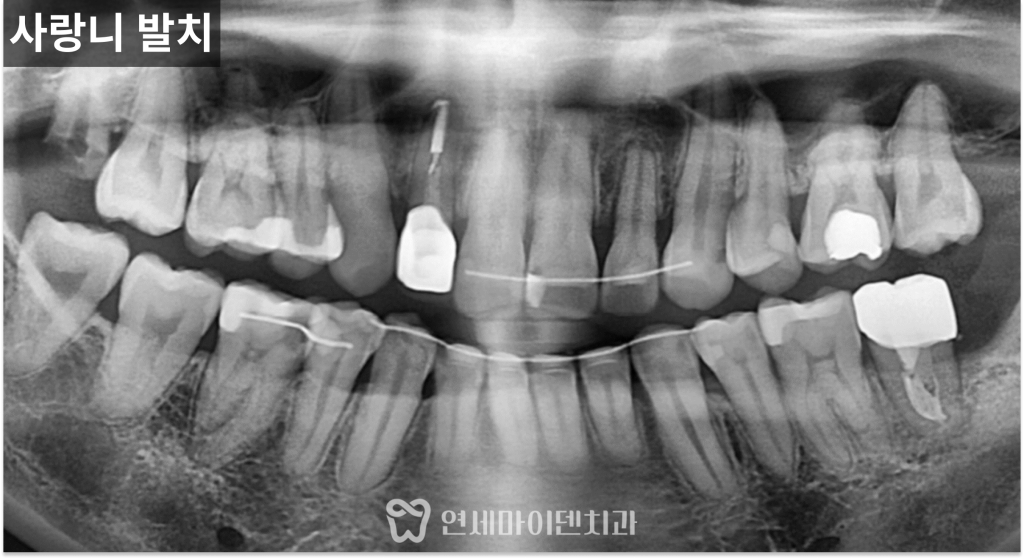

또한 원인이 되었던 사랑니는

발치를 진행했고,

반대편 사랑니 역시

추후 동일한 문제가 발생할 가능성을 고려해

함께 정리했습니다.

치료 후에는 인접 치아의 충치까지

함께 정리하고

정기적인 검진을 통해 관리 중입니다.